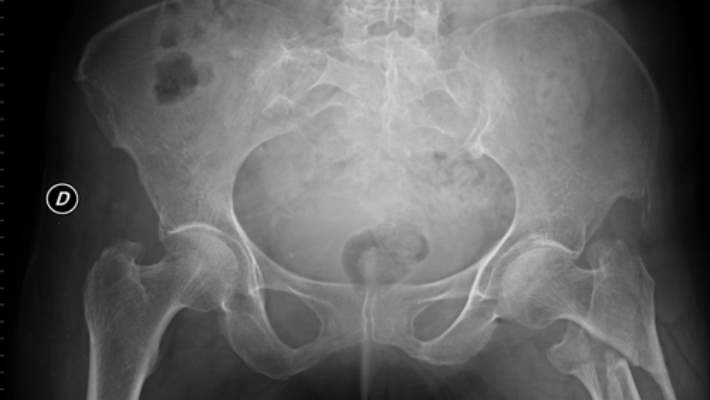

6 - 8 aylarda (kalça topunda kemikleşme başlaması bebekten bebeğe değişen zamanlamalarla oluşur) direkt röntgen incelemesi yeterli bilgiyi vermektedir.